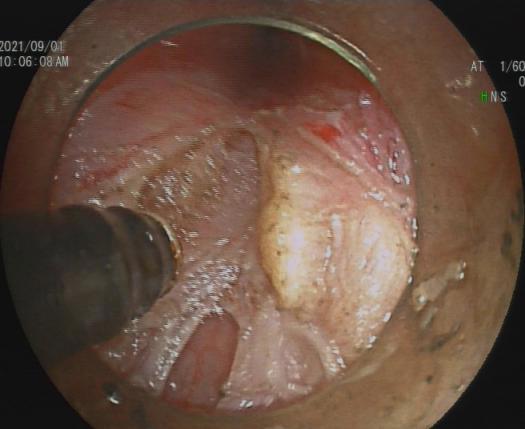

3.早期消化道肿瘤ESD技术

内镜下粘膜剥离术(ESD),具有超级微创、安全性高、住院时间短及费用低等优势,治疗早期胃癌、食管癌、大肠癌等病变,5年生存率超90%。

直肠巨大绒毛状腺瘤 内镜下粘膜剥离过程

粘膜剥离术后创面 剥离的巨大腺瘤